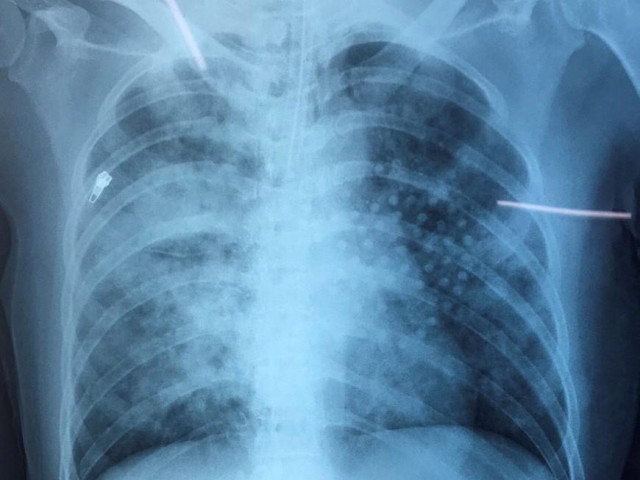

TS.BS Lê Ngọc Duy – Trưởng Khoa Cấp cứu và Chống độc, Bệnh viện Nhi Trung ương cho biết, trẻ nhập viện trong tình trạng suy hô hấp, có dấu hiệu tổn thương thần kinh kèm theo sưng nề trán và mắt trái do ngã. Sau khi tiến hành cấp cứu và làm các xét nghiệm lâm sàng và chụp CTscan sọ não, cháu được chẩn đoán suy hô hấp/vỡ xương trán hốc mắt trái. Sau 1 ngày điều trị tích cực hiện sức khoẻ trẻ tiến triển tốt, rất may không để lại di chứng thần kinh trong quá trình cấp cứu ngừng tim, trẻ sẽ được xuất viện về tuyến dưới theo dõi thêm cho tới khi sức khoẻ ổn định xuất viện về nhà với gia đình.